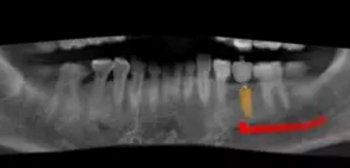

術(shù)前術(shù)后CBCT數(shù)據(jù)對比分析,植體就位準確。

根據(jù)上述植入和修復(fù)方案,立體設(shè)計Implant Guide™全程導(dǎo)板,鑒于下頜需避讓下頜神經(jīng)管,并考慮到種植體與頰舌側(cè)、近遠中側(cè)的關(guān)系,設(shè)計在該牙位植入1顆Alpha-Bio Tec ICE 4.2x 10mm的植體。

術(shù)前,導(dǎo)板設(shè)計工程師,根據(jù)CBCT以及模型數(shù)據(jù),將患者的解剖結(jié)構(gòu)、軟組織形態(tài)和修復(fù)效果數(shù)字化三維重建,在設(shè)計軟件內(nèi)進行虛擬修復(fù)體冠設(shè)計,同時與臨床醫(yī)生一起,根據(jù)#35牙槽骨高度以及寬度,結(jié)合下牙槽神經(jīng)管,設(shè)計好合適的種植位點。